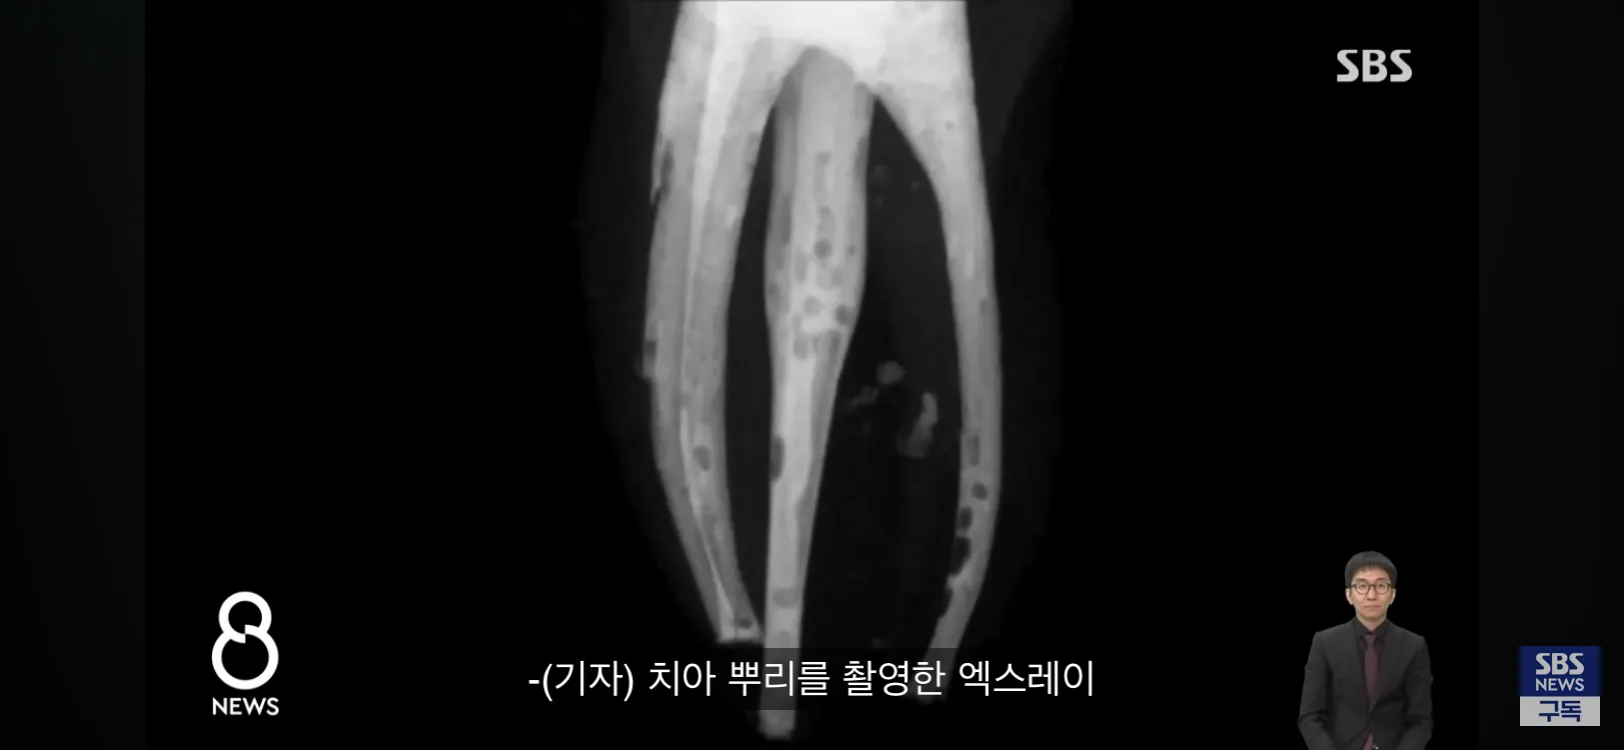

치아 뿌리가 보이는 치과 엑스레이 사진

신경 치료 충전재 기포 발생 비교 엑스레이 이미지